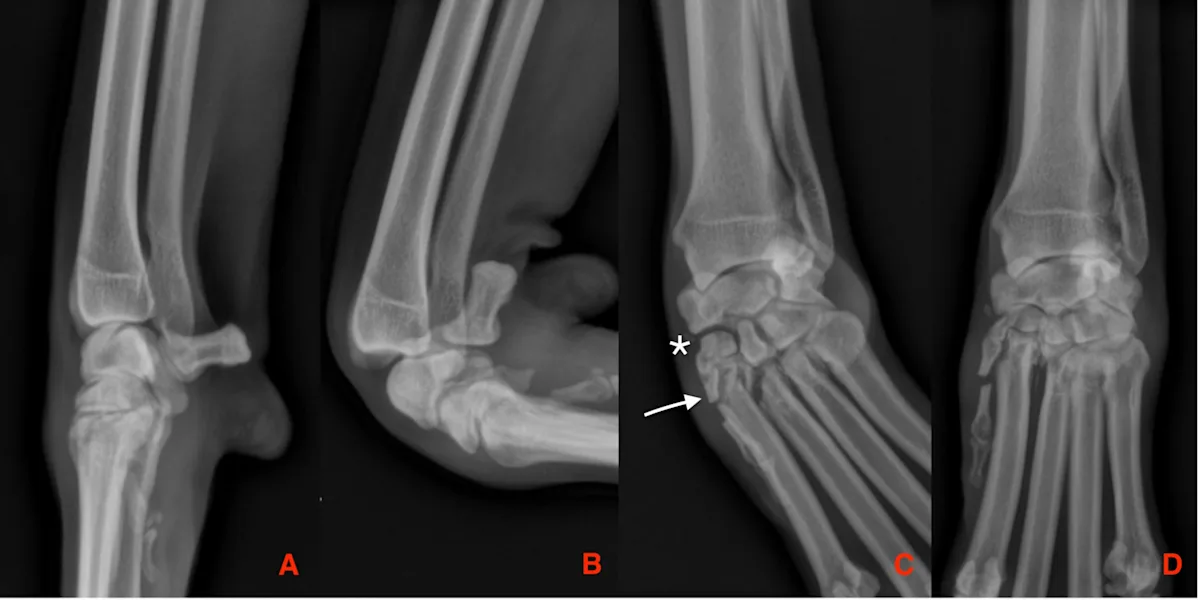

FIGURE 6

Radiography was performed on a 10-year-old spayed rough collie with acute lameness of the left thoracic limb after chasing a cat. Stress was applied with the carpus in extension (A), flexion (B), valgus (C), and varus (D). Lateral (A, B) and dorsopalmar (C, D) views of the carpus are provided. Visible joint widening (C, asterisk) can be visualized between the radial carpal and second carpal bones, and a comminuted fracture of the proximal aspect of the second and third metacarpal bones is present (C, arrow).